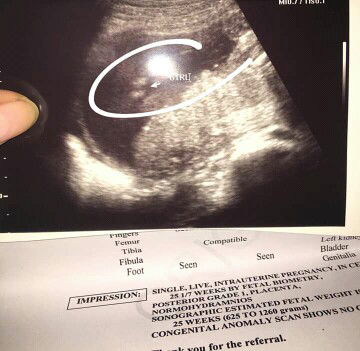

male or female

Ano po ba talaga??